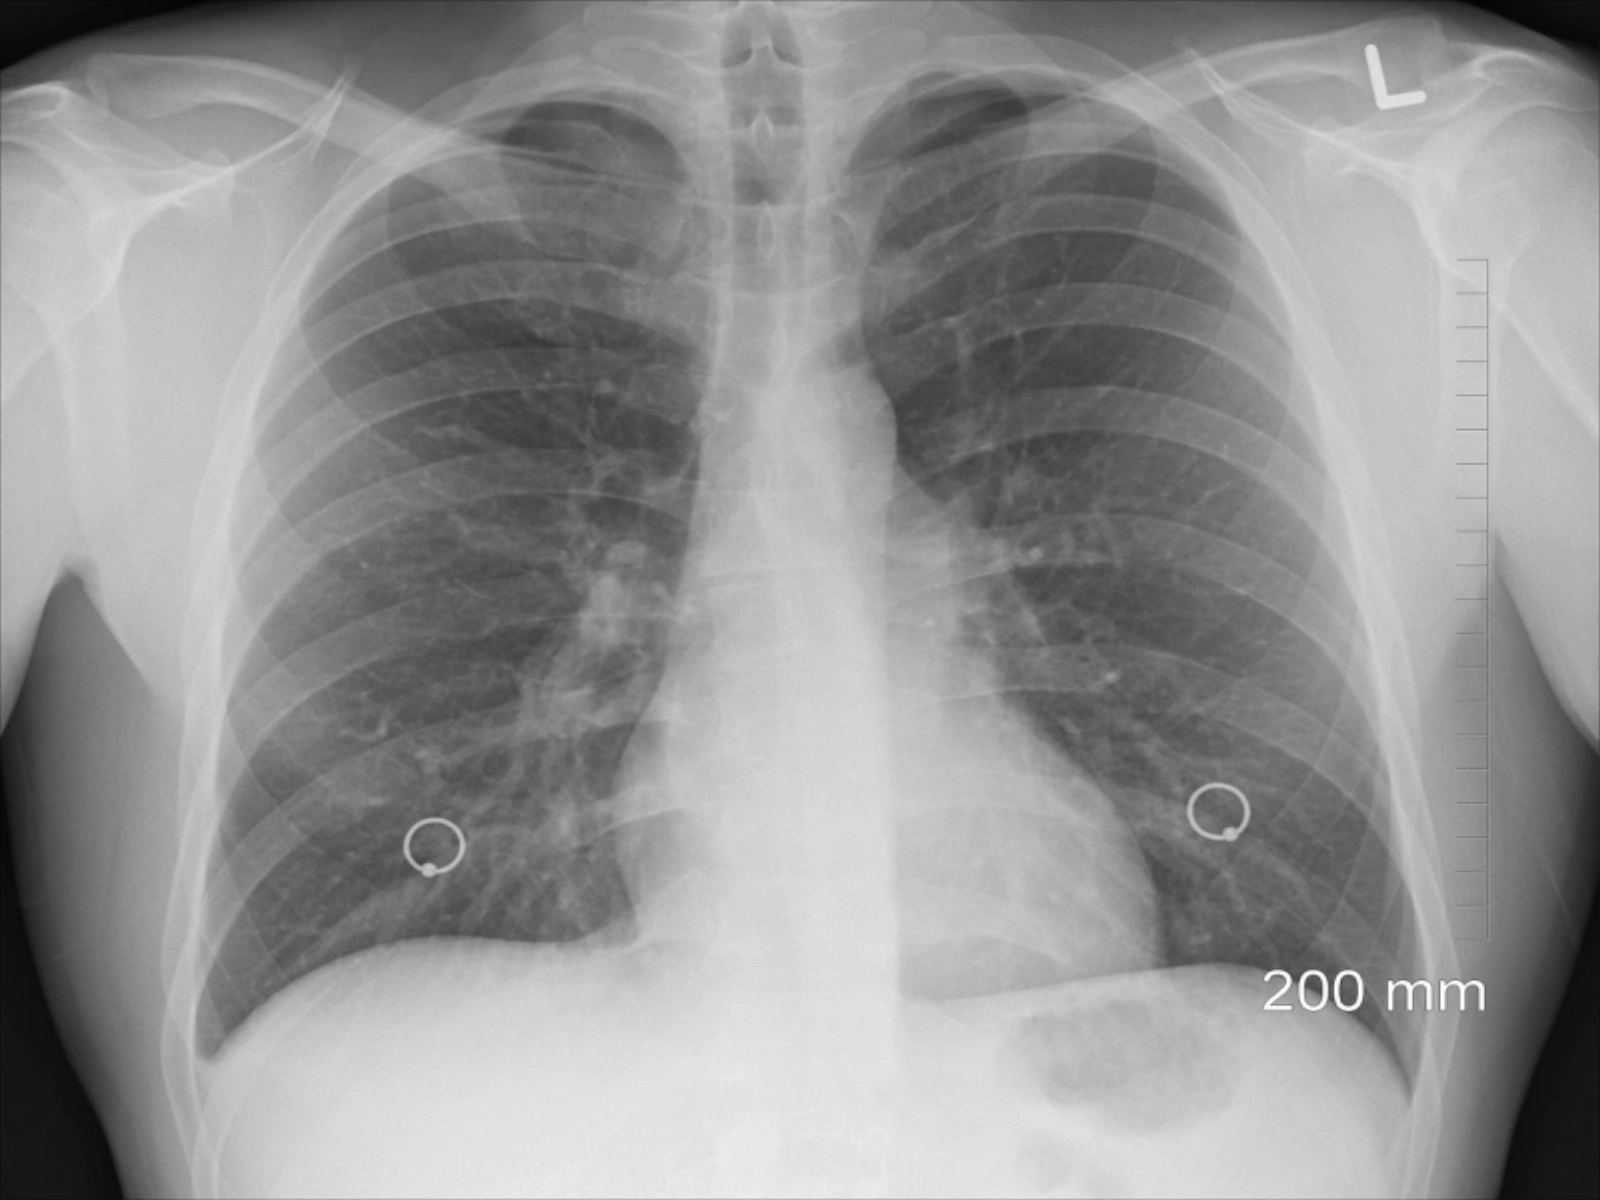

Aceştia explică faptul că aparatul a fost achizitionat urmare a solicitărilor secţiei ATI şi a conducerii SJUSM, prin fonduri ale Ministerului Sănătăţii în 2023 şi a fost folosit în sectia ATI a SJUSM pentru prima dată la o tânără de 49 de ani cu ARDS sever fără antecedente patologice.